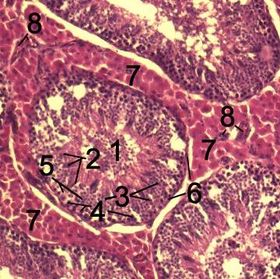

![]() Histological section through testicular parenchyma of a boar. 1 Lumen of Tubulus seminiferus contortus 2 spermatids 3 spermatocytes 4 spermatogonia 5 Sertoli cell 6 Myofibroblasts 7 Leydig cells 8 capillaries | |